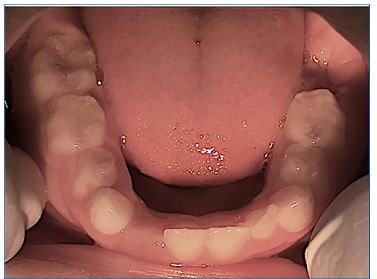

Intraoral examination revealed the presence of gingival hyperplasia in the upper arch and gingivitis associated with the presence of dental biofilm, arched palate, Angle class I occlusion without crossbite or open bite, dolichofacial pattern, labial hypotonia, and mild enamel hypomineralization (presence of whitish-cream demarcated opacities)14 in the permanent maxillary central incisors (Figures 4 and 5). Moreover, she had caries lesions in the deciduous mandibular left second molar and mandibular first permanent molar, which presented great coronary destruction and pulp involvement (Figures 6 and 7).

Figure 7 View of the lower arch, showing the extraction performed and the carious lesion on the left second deciduous molar